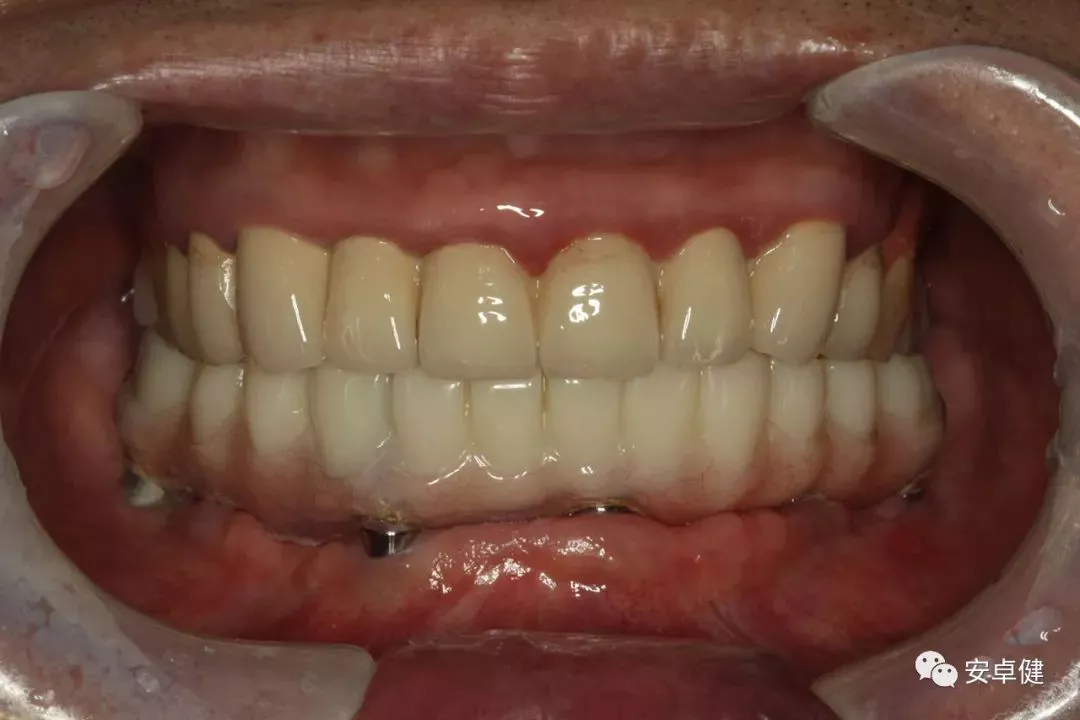

▷ 永久修复

患者术后16个月:

• 于口内试戴原厂纯钛切削一体式桥架,并检查前牙排蜡外形及后牙咬合关系;

• 聚合瓷烤塑制作最终修复体;

• 为减少牙面磨耗,于后牙区制作360度防裂纯钛金属带;

• 试戴满意后,二级螺丝加力至15N;

• 特氟龙封闭螺丝孔,光固化复合树脂封闭上方螺丝通道,完成最终固定式种植义齿修复;

• 修复体外形能够正确恢复面下1/3高度及侧貌;

• 患者可获得较为稳定的咬合关系,并满足其咀嚼功能的需求;

• 患者42、46部位牙龈退缩,缺乏足够的角化龈,为方便后期清洁维护,选择穿龈较高的龈上肩台;

• 口内观察,修复体边缘金属基台颜色暴露,但由于其处于下颌后牙非微笑暴露区,故对临床整体美观效果的影响在患者可接受范围内。

最终修复后8个月

戴牙后8个月复诊正面咬合照

• 随访可见患者口腔卫生状况可,牙龈无红肿;

• 下颌修复体状态良好,无修复体机械并发症;

• 种植体基台稳定性良好,无松动;

• 种植体无松动,周围无红肿、溢脓及疼痛表现;

• 正中、前伸及侧方咬合检查可见咬合印记分布均匀,咬合关系良好;

• 患者反映日常使用良好,舒适性佳,满意度高。